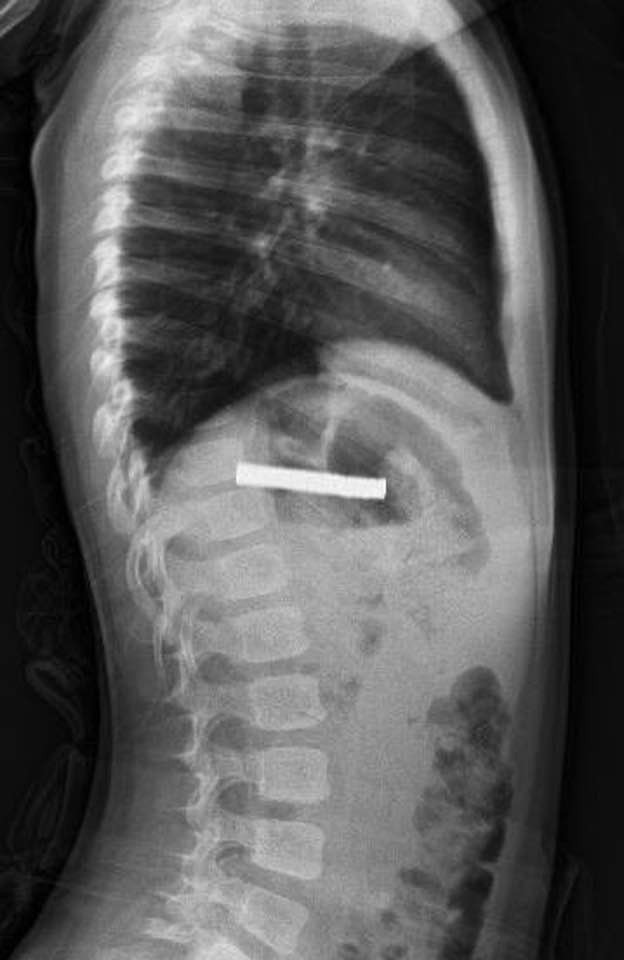

Edinilen bilgiye göre, Erzurum’da bir çocuk evde bulunan 19 tane mıknatısı yuttu. Çocuğun rahatsızlanması sonucu durumu öğrenen aile hastaneye başvurdu. Daha sonra çocuk Elazığ’a sevk edildi.

Fırat Üniversitesi Çocuk Gastroenteroloji Hepatoloji ve Beslenme Bilim Dalı Başkanı Prof. Dr. Yaşar Doğan, çocuk hastanın yemek borusuna yapışmış 19 mıknatısı endoskopik yöntemle çıkardı.

Mıknatıslar uzun süre yemek borusunda takılı kaldığı için yemek borusu ve mide girişinde zedelenmeler olurken, çocuğun sağlık durumunun iyi olduğu ve taburcu edildiği öğrenildi.